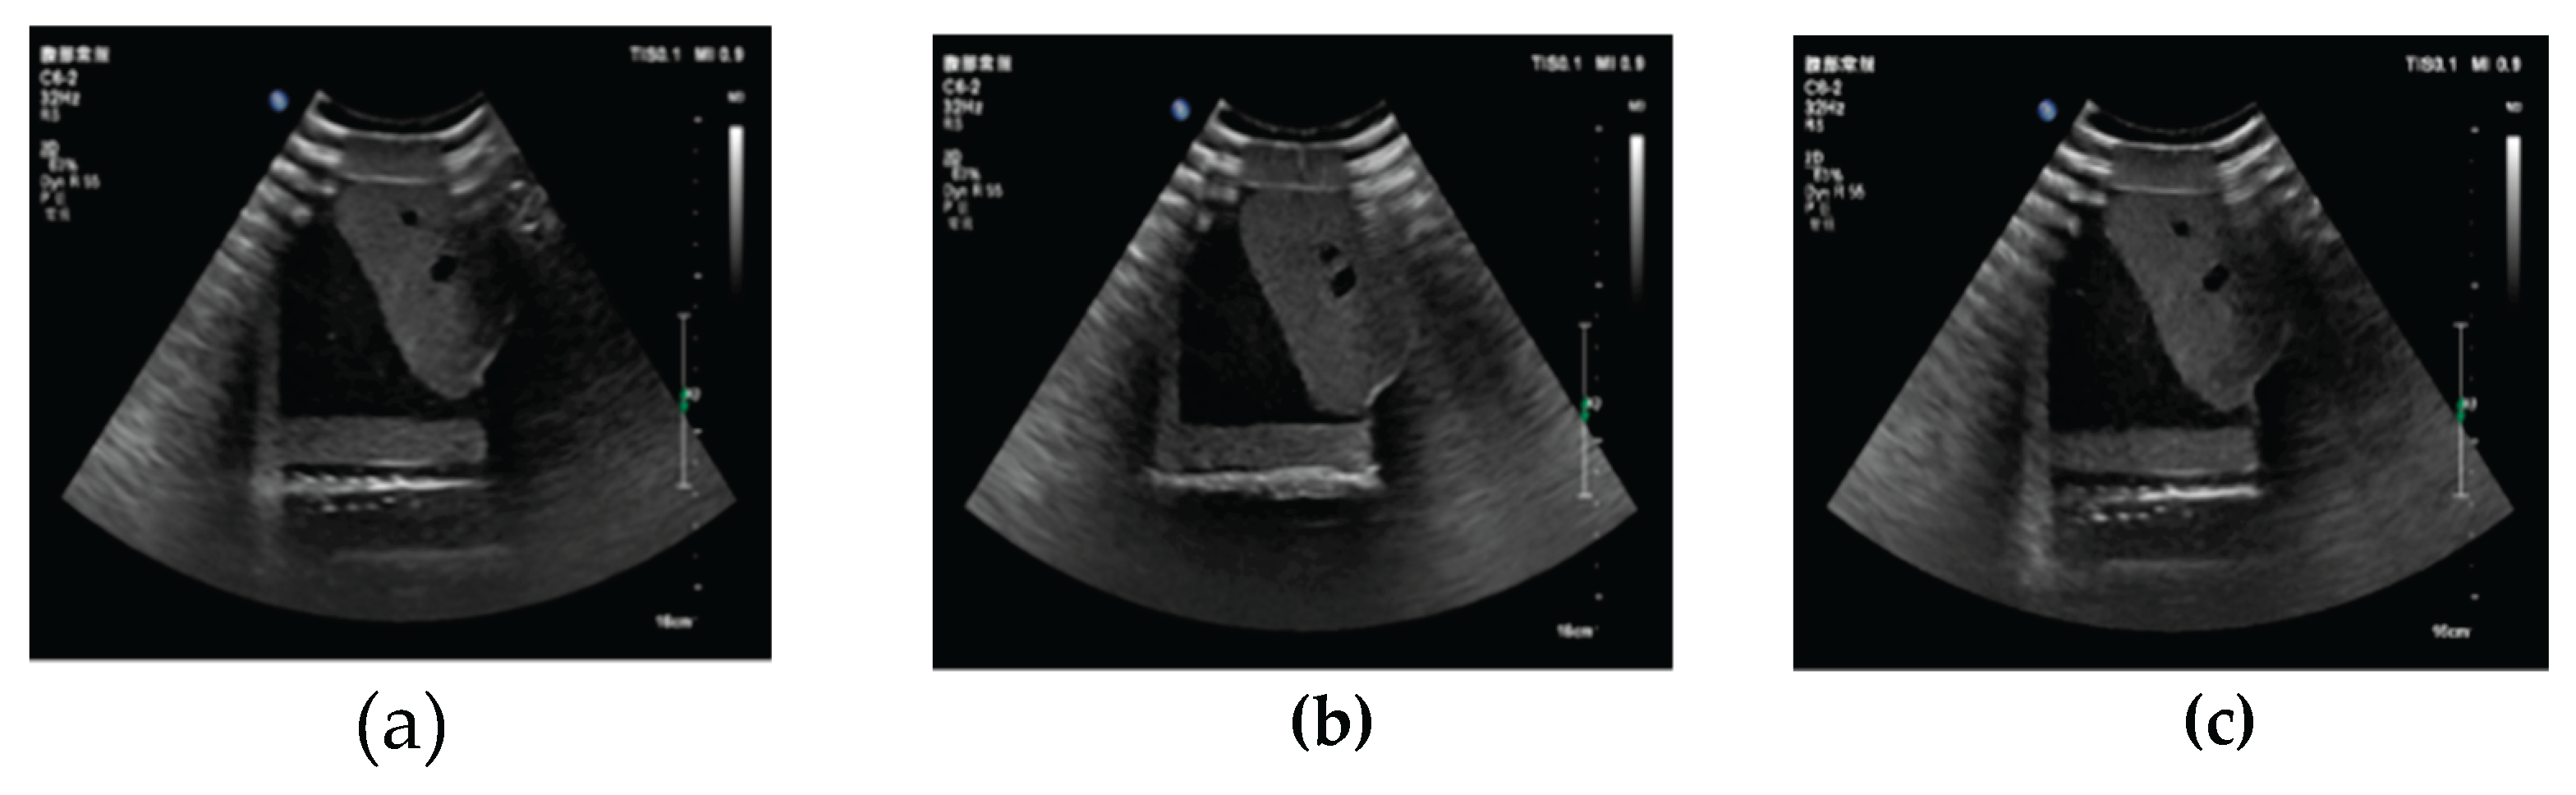

3.1. Three-Dimensional Reconstruction Results of Local Liver Ultrasound

3.2. Image Segmentation and Recognition Results